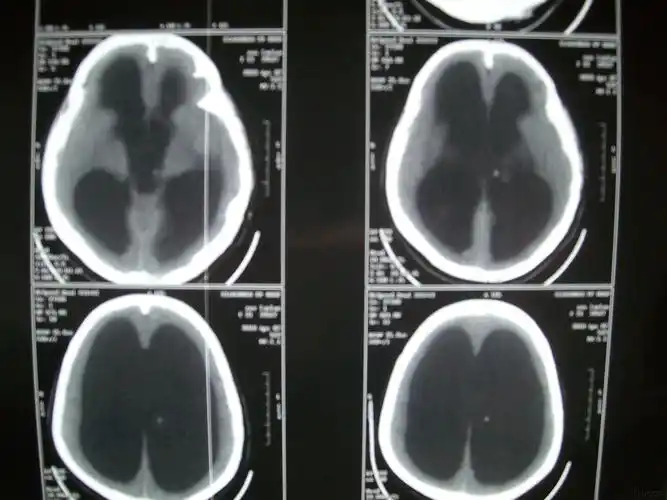

脑积水ct显示:侧脑室,三脑室扩大有症状的脑积水应该及时手术治疗.

脑积水ct影像

交通性脑积水(正常颅压性脑积水)vp分流治疗一例